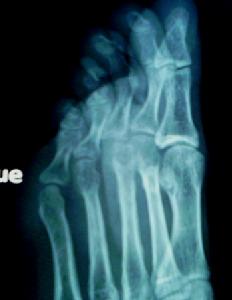

1、X線檢查對本病確診有特殊價值,表現為管狀骨造型失常,骨質吸收,骨折;骺板改變及軟組織腫脹;骨幹處骨膜下新骨形成;顱縫增寬,前囟飽滿擴大。

4、X線特點:管狀骨改變,骨膜下新骨形成,骨膜增生,嚴重者出現骨骺包埋畸形,使骨骺與骨幹過早閉合,頭顱改變,顱縫增寬,前血囟擴大。